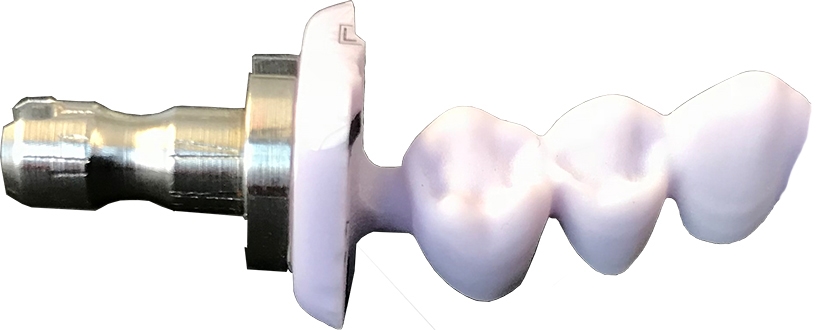

Implants / Abutments

Implants are cylinders made of titanium or ceramics which are implanted into the jaw bone in place of the missing tooth root. They are the foundation of an implant crown or bridge.

An implant and a crown mimic the form and function of a natural tooth.

The implant is connected to the crown with an abutment. The abutment allows the crown to be securely attached.

Nowadays, customized (patient-specific) abutments are standard of care. Abutments can be made out of one or two pieces. One piece abutments are usually made out of a single material such as titanium or zirconia. Two piece abutments are usually made out of a combination of materials. For example, they may have a titanium base and a ceramic abutment or crown with a screw access hole on top.

With the machines described on this website, you are only able to use prefabricated abutments or mill / grind the top part of a two-piece abutment. Processing other abutments and all types of implants is not possible.